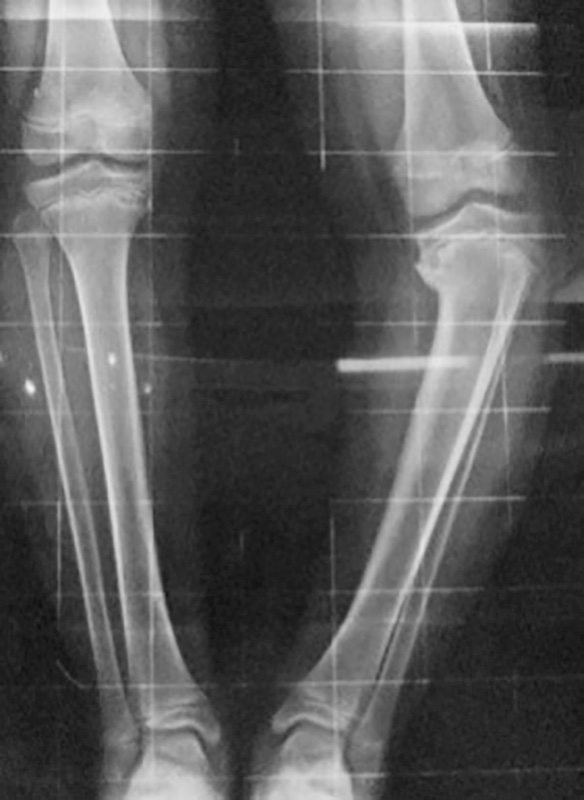

La forma più comune è rappresentata dal ginocchio varo dell’infanzia, generalmente bilaterale e completamente asintomatico, caratterizzato da una persistenza della deformità dopo il primo anno di vita, con l’inizio della deambulazione. La patogenesi sembra correlata ad un transitorio alterato ritmo di ossificazione fra la porzione interna ed esterna delle cartilagini di accrescimento distale del femore e prossimale della tibia. Clinicamente è presente un incremento della distanza intercondiloidea interna che può essere più o meno accentuata e viene valutata in centimetri a livello del ginocchio (Fig. 1).

In questi casi, per escludere la presenza di altre patologie, è necessario praticare un esame radiografico del bacino e degli arti inferiori, nei bambini più piccoli anche fuori carico, per valutare oltre all’entità del varismo la coesistenza di patologie associate che interessano le cartilagini di accrescimento del ginocchio (Fig. 2).